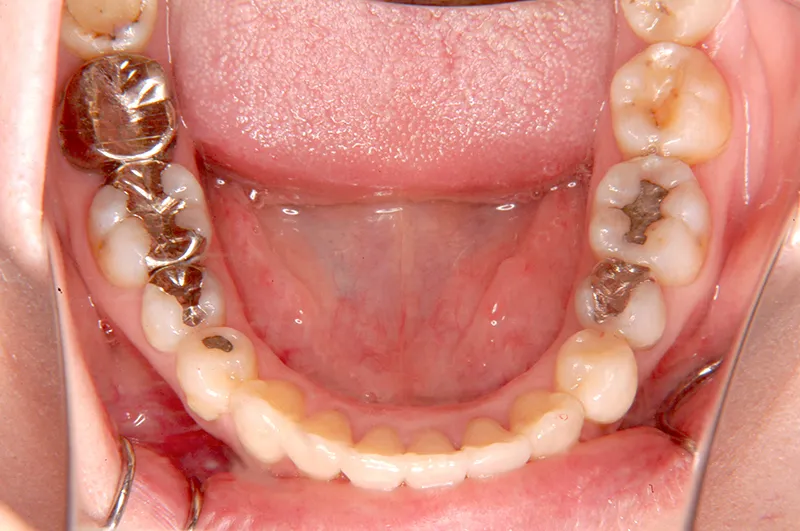

初診時年齢 40歳以上 (女性) 主訴 上下のがたがた・噛み合わない

診断名 叢生 装置名

特徴 ゆがんで生えている

状態 ガタガタ・でこぼこに生えている(叢生)

上下のがたがたと噛み合わない事を主訴に来院されました。

初診